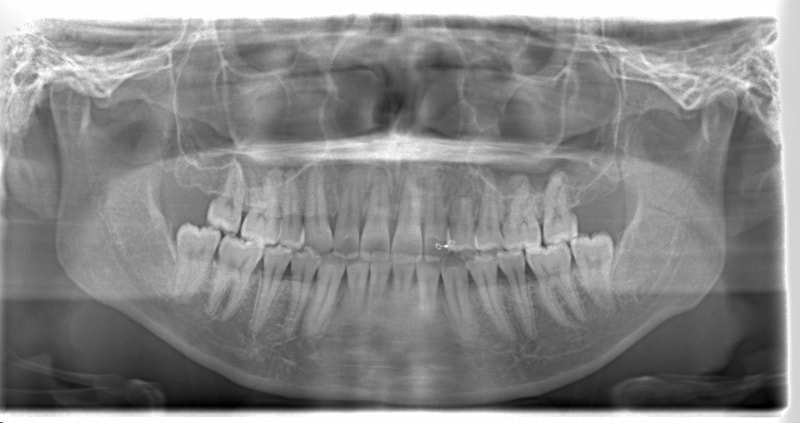

左上3番埋伏歯

治療法:フルパッシブブラケット:T21